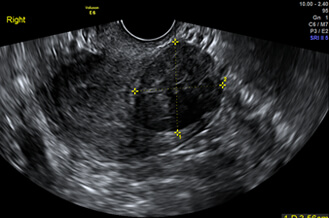

Conception may be affected by many factors, such as uterine myomas, chocolate cysts, endometrial thickness, and the number of antral follicles. All of these can be gathered by vaginal ultrasound scans.

chocolate cysts